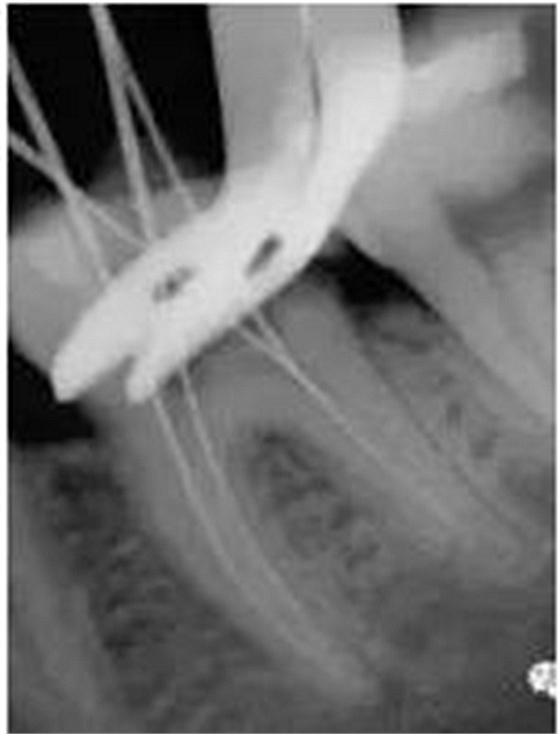

2、讓X線片貫穿治療的全過(guò)程

術(shù)前、確定長(zhǎng)度、根管預(yù)備后、試尖、充填后都要有X先片的跟蹤,而且數(shù)字化X線片絕對(duì)是很值得的投資,會(huì)讓根管治療提升一個(gè)檔次,既增加了精確度,又節(jié)省大量的時(shí)間。從一個(gè)高質(zhì)量的術(shù)前X線片中,可以解讀出很多的內(nèi)容:

①是否為治療齒(這點(diǎn)很關(guān)鍵)

②髓腔以及根管的大致形態(tài),有些復(fù)雜的MB2及C型根還需要有CT和顯微鏡的幫助。

③根充物情況:種類、位置

④牙周以及根尖周組織的病變情況,等等